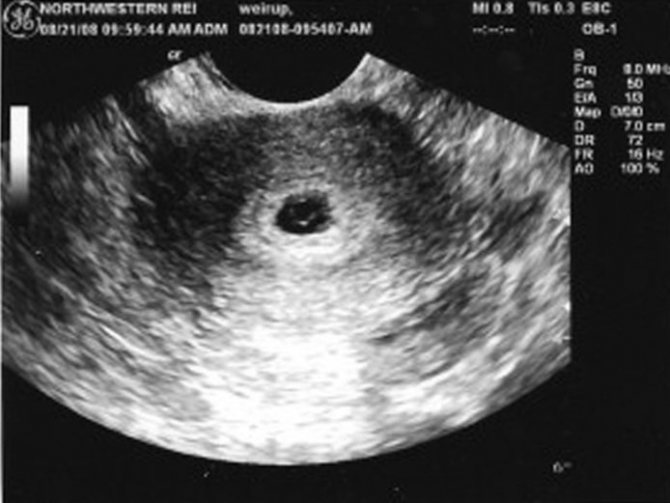

УЗИ: пышный эндометрий — беременность

Пышный эндометрий – это утолщенный функциональный слой эндометрия, который часто сигнализирует о беременности. Вместо того, чтобы отторгнуться и выйти во время менструации, эндометрий утолщается, количество кровеносных сосудов увеличивается, создавая благоприятные условия для существования эмбриона. Эндометрий утолщается к концу цикла в любом случае, а затем либо отторгается, либо помогает эмбриону, вышедшему из яичника, закрепиться в матке и обеспечивает его питанием и защитой.

Пышный эндометрий не имеет симптомов, увидеть его можно во время УЗИ еще до того, как начнет просматриваться само плодное яйцо. Маленький эмбрион может прятаться в этом пышном эндометрии.

Пышный эндометрий при беременности чаще всего указывает на ранние сроки, однако причины могут быть и иные. На таких ранних сроках, когда плод еще не виден (3 недели после зачатия), УЗИ не может гарантировать 100% точность. Врач после УЗИ советует чуть подождать и сделать тест на беременность или же сдать кровь на определение уровня ХГЧ. Если тест отрицательный, следует продолжить обследование и выявить причины увеличения клеток эндометрия.